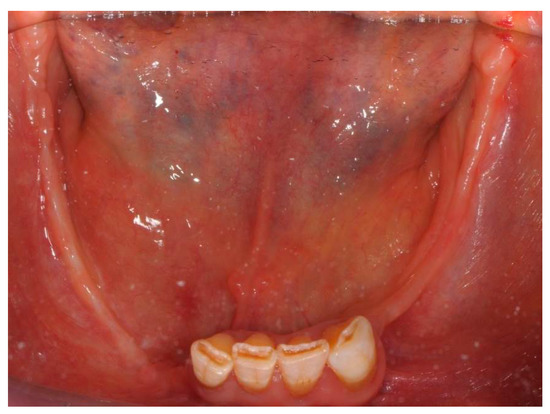

2. Case Report